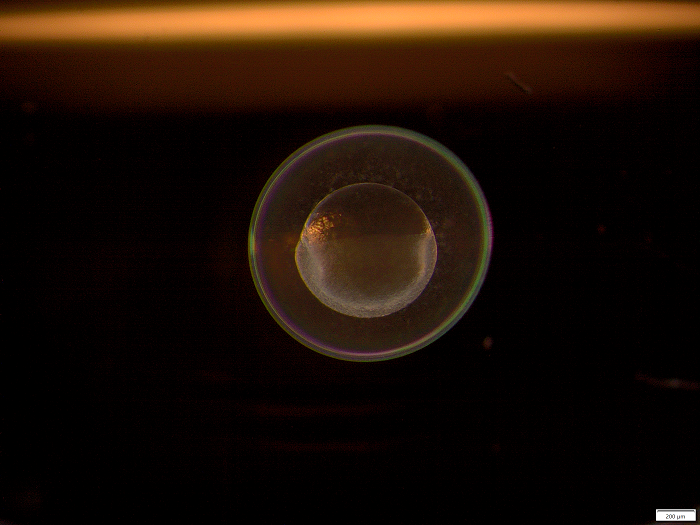

Artificial heart tissue pulled onto plastic rods to measure its elasticity (Photo: M. Gotthardt, MDC)

Dr. Michael Radke, a lead author of the study, first successfully tested the ASOs in mice with stiffer heart walls. His colleague Victor Badillo Lisakowski then grew heart muscle cells derived from human stem cells into artificial heart tissue. The tiny 3D structures can be stimulated to contract and relax when they encounter resistance, enabling them to mimic the pumping action of the heart. This artificial heart tissue also showed what effect the treatment had: The researchers were able to demonstrate that the ASO molecules actually penetrate the cells and trigger the desired response. “These tests on artificial heart tissue were an important step, because the primary sequences for titin are not identical in mice and humans,” says Radke.